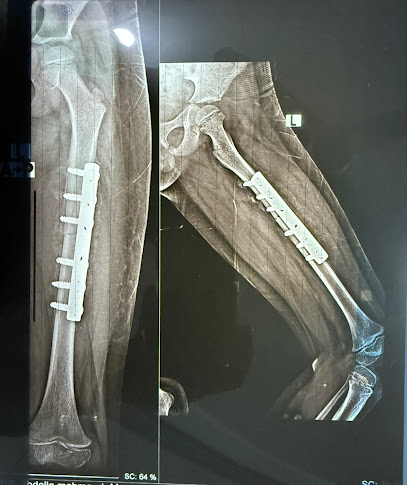

Dr Mostafa Emad Clinic هي عيادة طبية تتخصص في جراحة العظام، حيث يعمل بها الدكتور مصطفى عماد الذي يعتبر خبيرًا في تقويم العظام. للحجز والاستفسارات، يُرجى الاتصال برقم الهاتف: 01008583877.